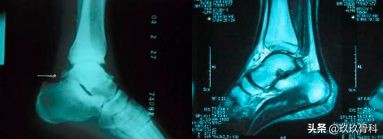

辅助检查

- X线 踝关节正侧位(必要时应加照踝穴位)

- B超

- MRI

应力位片